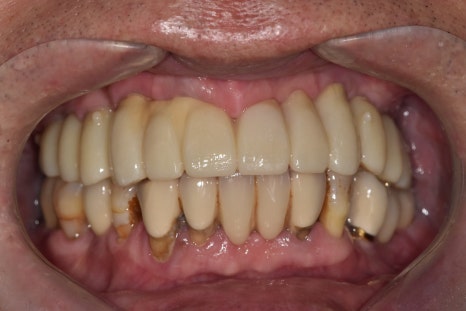

250510

짠! 치아가 훨씬 자연스럽게 나왔습니다.

치아의 잇몸 쪽을 핑크포세린으로 덮어 자연스럽게 잇몸처럼 표현했습니다.

상악동 거상술의 가장 큰 성공 요인 중 하나는 얇은 막이 찢어지지 않게 하는 건데요.

일반 뼈이식보다 난이도가 있다는 뜻입니다.

그러다 보니, 일반 치과에서 종종 치료를 거부하거나

대학병원으로 의뢰하는 경우가 있습니다.

이 환자분의 경우도 같은 상황이셨습니다.

다행히 저희 병원에서 치료를 잘 마칠 수 있도록

도와드려서 정말 다행입니다.